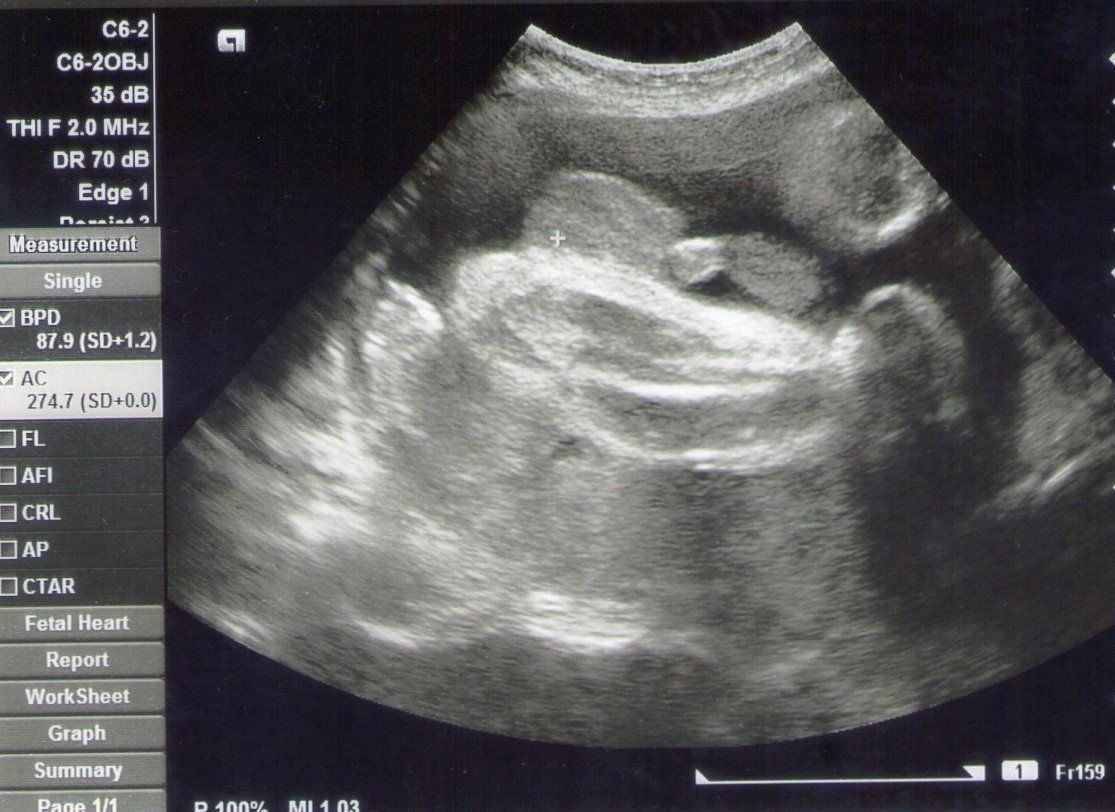

妊娠34週目のエコー写真 胎児が初めて2kg超え

一番白くはっきり写っているのは赤ちゃんの足の骨です。かなり太く、しっかりしてきました。小さく丸く写っているものがあったので、男の子であることも再確認できました。産院主催のお産の勉強会に参加して、いよいよ出産が近づいてきたと感じました。この時期には、夜中におなかが張ることが多くて、よく起きてしまいました。